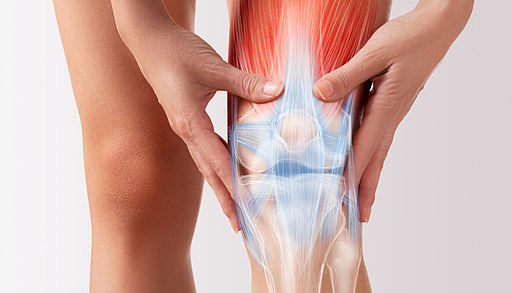

무릎 연골 손상 증상 및 치료방법

무릎 연골 손상 증상들은 망가진 연골 부위의 염증 반응때문에 반복적으로 붓기도하며 오랜시간동안 한자세로 앉아 있다가 나타날 때 관절이 굳어진것같은 느낌과 무릎이 구부러지거나 펴지지 않다가 급격히 움직이기도 한다고 해요.

무릎의 연골도 대부분 관절과 동일하게 뼈를 매끄럽고 마찰이 덜가게 생성해 주는 미끄러운 연골 층으로 둘러 축적되어 있어요. 뿐 아니라, 무릎 중앙에는 부가적인 충격 흡수를 전달하는 반월상 연골이라고 하는 두 개의 고무질 반원형 연골 조각이 있어요.